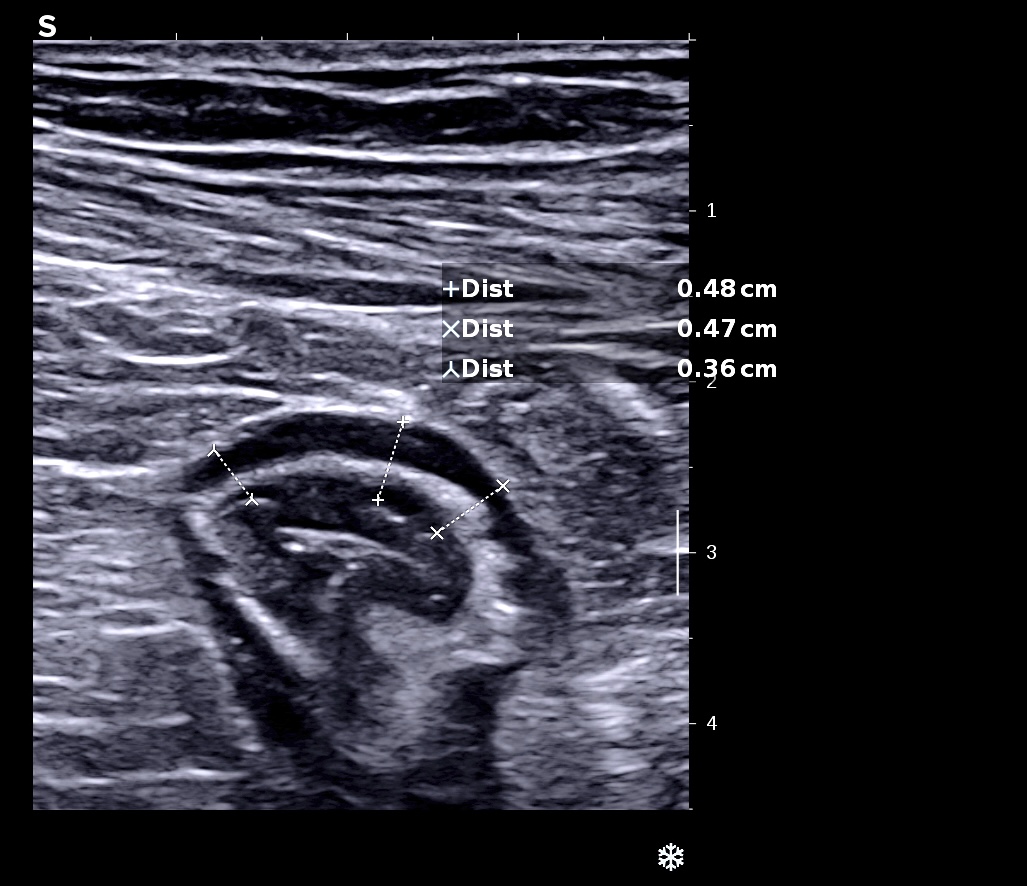

Muqueuse épaissie en coupe transversale

L'épaississement prédomine à la 3 ième couche hyperéchogène( > 1/3 de la paroi), il est continue, régulier, cironférentiel

La structure en couche est conservée

La graisse est peu infiltrée, l'activité doppler modérée.